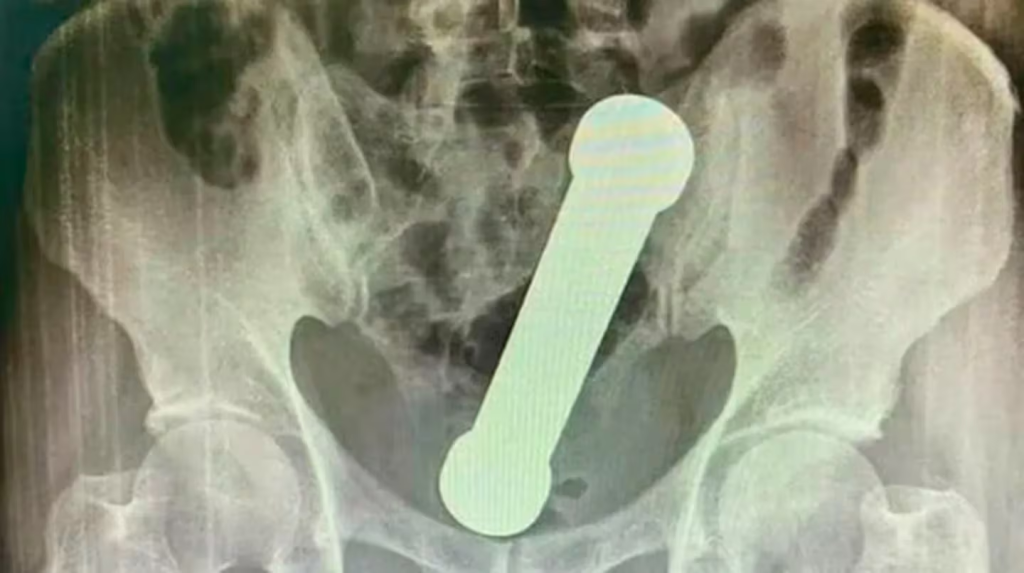

En aquel momento, la víctima, de 54 años, se presentó en un hospital de la ciudad Manaos, noroeste de Brasil, con dolor abdominal, náuseas y dificultad para defecar. Le hicieron una radiografía que mostró que tenía un objeto de metal de 4,4 libras y casi 20 cm en el ano.

En ese entonces, los médicos revelaron que se trataba de una práctica sexual. Afirmaron que tuvieron que actuar rápido para evitar una perforación anal u otra lesión grave.